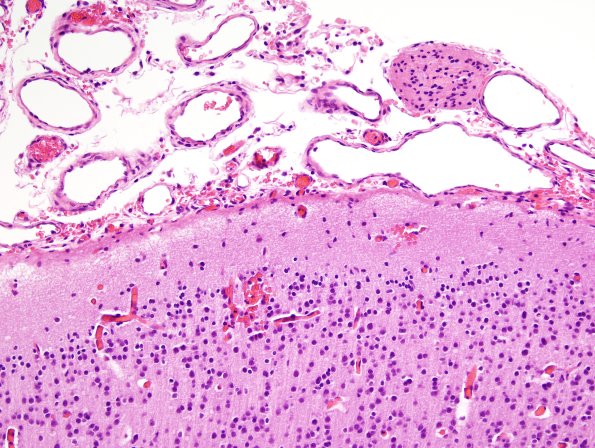

Washington University Experience | DEVELOPMENTAL MALFORMATIONS | Encephalocele | 8C4 Encephalocoele (Case 8) H&E 7

In some areas there are glioneuronal heterotopias in the leptomeninges as well as subcutaneous glial heterotopic islands. (H&E)